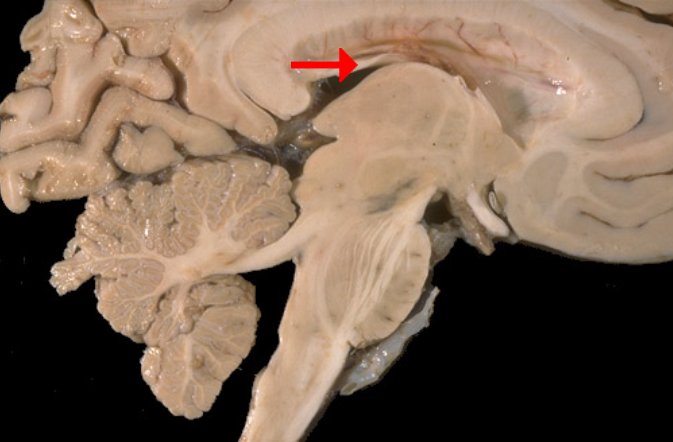

Label this brain part

Fornix